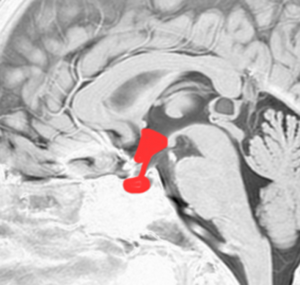

視床下部と下垂体を横から見たところ

- 視床下部と下垂体の大まかな拡大図です。視床下部から視床下部ホルモンと神経伝達が出て,下垂体茎(下垂体柄とも言います)を伝わって,下垂体の前葉と後葉からホルモンが血液の中に出て体中に広がります。

- 視床下部には食欲の中枢とか,睡眠の中枢とか,体の中の水分や塩分の調節をする中枢とか,体内時計とか,いろいろ複雑でな高度な働きがあります。

- 下垂体の前葉からは,成長ホルモン GH,プロラクチン PRL,甲状腺刺激ホルモン TSH,副腎皮質刺激ホルモン ACTH,性腺刺激ホルモン LH & FSHなどが出ます。

- 下垂体の後葉からは,おしっこの量を調節する抗利尿ホルモン ADHというのが出ます。